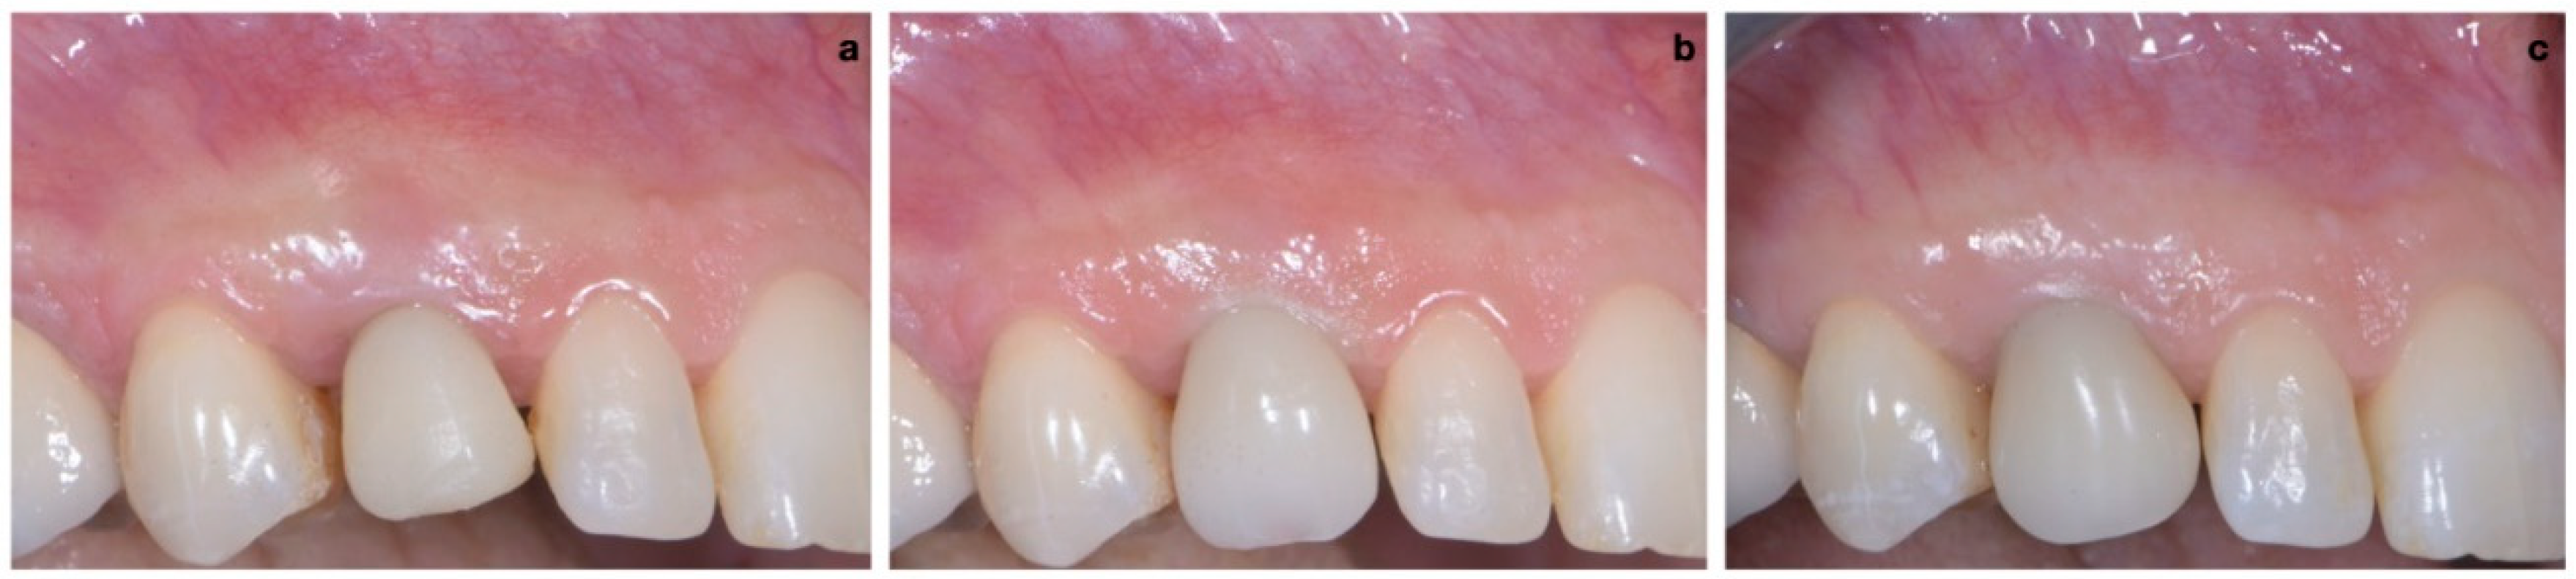

A 40-year-old patient presented with an endodontic fistula on the maxillary right canine (Figure 1a–c). Radiographic evaluation revealed internal root resorption (Figure 2). The medical history did not include any systemic conditions contraindicating implant placement or regenerative surgery. The patient did not suffer from any form of periodontal disease. Due to the extension of root resorption, the tooth was considered irrational to treat, and the treatment plan consisted of extraction and immediate implant positioning.

2.3. Provisional Restoration

As shown in Figure 13, the maturation of soft tissue at 1 month (a), 3 months (b) and 6 months (c) after surgery was evident. The peri-implant soft tissues were conditioned with the provisional crown until the shape and position for the mucosal scallop to resemble the gingival margin of the adjacent corresponding tooth and the progressive growth of peri-implant papillae were obtained [19]. In this phase, the patient was called every 2 weeks for us to check the provisional restoration. At the end of the conditioning phase, it was possible to place the definitive, screw-retained restoration (Figure 14a–c).

Figure 1. (ac) Forty-year-old patient with endodontic fistula on maxillary right canine.

Figure 13. Maturation of soft tissue at 1 month (a), 3 months (b) and 6 months (c) after surgery.